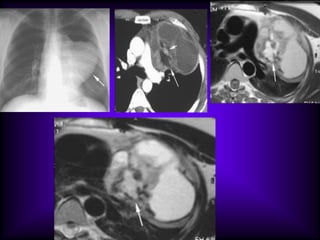

Mediastinal Cysts

The CT features of benign

mediastinal cyst are

(a) a smooth, oval or tubular mass with a well-

defined thin wall that usually enhances after

intravascular administration of contrast

material,

(b) homogeneous attenuation, usually in the

range of water attenuation (0–20 HU),

(c) no enhancement of cyst contents, and

(d) no infiltration of adjacent mediastinal

structures.

Cysts that contain serous fluid typically have

long T1 and T2 relaxation values, which

produce low signal intensity on T1-weighted

MR images and high signal intensity on T2-

weighted images.

Because cysts containing nonserous

fluid can have high attenuation at CT,

they may be mistaken for solid

lesions. MR imaging can be useful in

showing the cystic nature of these

masses because these cysts continue

to have characteristically high signal

intensity when imaged with T2-

weighted sequences regardless of the

nature of the cyst contents